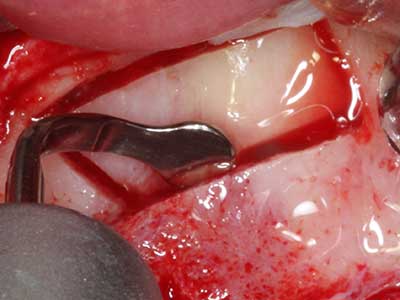

Fig. 18: Preparation of a cortical cover with the piezo bone saw (Piezomed, W&H).

Fig. 19: Surgical site after neurolysis and removal of osteoma.

Fig. 20: The removed bone cover is re-adapted and fixed with an osteosynthesis screw (KLS Martin, Tuttlingen).